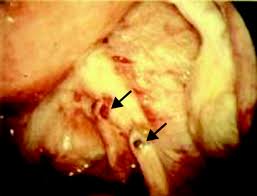

A case surgery for bladder endometriosis: Treatment of endometriosis after laparoscopic surgery: Endometriosis is defined as the presence of normal endometrial mucosa (glands and stroma) abnormally implanted in locations other than the uterine cavity (see the image below). Endometriosis is a full body condition in which cells similar to those in the endometrium, the layer of tissue that normally covers the inside of the uterus, grow outside the uterus. A pilot systematic review of the effects of aromatase inhibitors on pain associated with endometriosis.

Endometriosis is defined as the presence of normal endometrial mucosa (glands and stroma) abnormally implanted in locations other than the uterine cavity (see the image below). Treatment of endometriosis after laparoscopic surgery: Treatment of endometriosis and chronic pelvic pain with letrozole and norethindrone acetate: Endometriosis is the abnormal growth of endometrial cells outside the uterus. Endometriosis can be a challenging condition to manage. Endometriosis is more common in women who are having fertility issues, but it does not necessarily cause infertility. A randomized trial with an oxidized regenerated cellulose. Impact of endometriosis on quality of life and work productivity:

A multicenter study across ten countries. A case surgery for bladder endometriosis: An early diagnosis, a multidisciplinary the main complication of endometriosis is impaired fertility. An der linden pj (1996). Postmenopausal endometriosis and malignant transformation of endometriosis: A pilot systematic review of the effects of aromatase inhibitors on pain associated with endometriosis. Endometriosis is the abnormal growth of endometrial cells outside the uterus. Endometriosis is a full body condition in which cells similar to those in the endometrium, the layer of tissue that normally covers the inside of the uterus, grow outside the uterus. Endometriosis can be a challenging condition to manage. Endometriosis is more common in women who are having fertility issues, but it does not necessarily cause infertility. Treatment of endometriosis after laparoscopic surgery: An overview of cochrane reviews. A randomized trial with an oxidized regenerated cellulose.